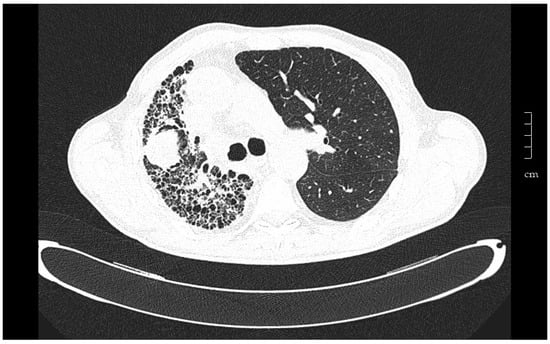

In unilateral transplant recipients, lung function stabilizes earlier, around the third month, because there is less surgical trauma []. The maximum pulmonary function reached is usually lower than in recipients of bilateral transplantation and depends on the characteristics of residual lung. In recipients affected by interstitial diseases the residual lung tends to collapse. After three months FVC and FEV1 can get over 80% of predicted values (Figure 1).

Figure 1.

Tomography of a 67-year-old man that underwent left unilateral lung transplantation for pulmonary fibrosis. The native lung tends to collapse, and the graft expands freely. Eight years after transplantation a tumor in the native lung was found in a follow-up chest scan. Ultrasound-guided fine needle aspiration puncture diagnosis was squamous cell carcinoma.